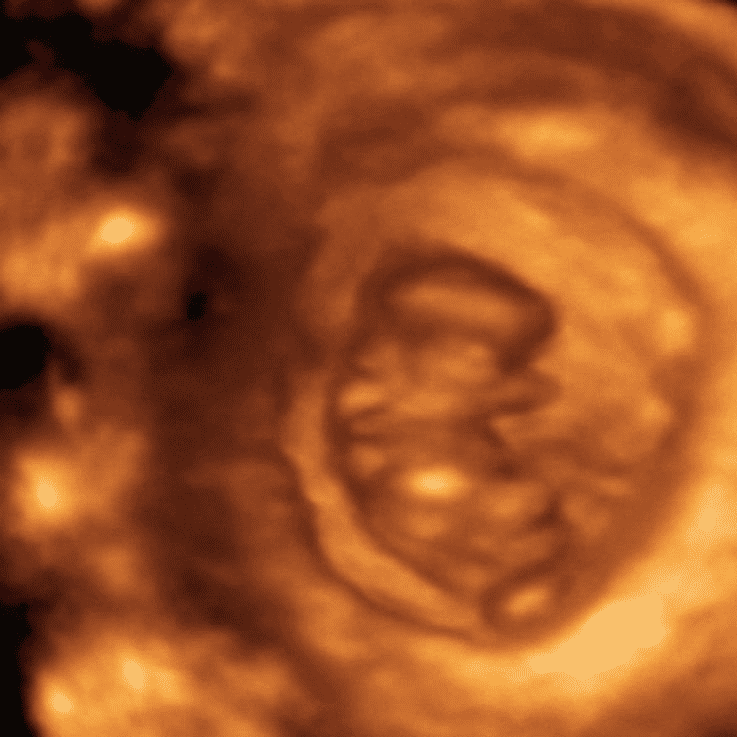

8 Weeks Ultrasound Scan – All Your Questions Answered – MyBump2Baby

Can You See Baby In Ultrasound At 8 Weeks – ababyw

Can You See Baby On Ultrasound At 8 Weeks – dbabyzi

8 Weeks Pregnant Ultrasound – Ultrasound at 8 weeks, 4 days | Ever …

The Pregnancy Diaries: I’m 8 weeks pregnant! – Life Education Council